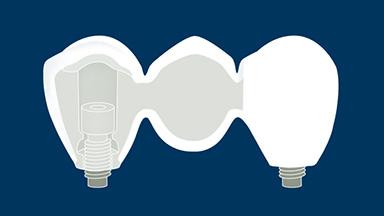

种植体支持式固定义齿旨在为缺失牙齿提供修复义齿,从而能承担相应的功能性需求,并且准确模拟缺失牙单位的美学效果。理想情况下,修复体应与周围牙齿难以分辨。为此,临床医生必须选择最佳的可用材料,来应对临床病情的种种挑战。本模块将讨论可用于制作种植体支持式固定义齿的牙科材料,以及为每个病例选择最合适的材料的基本原则。

- 描述用于制作种植体支持式固定义齿 (FDP) 的牙科材料的理想特性

- 罗列可用于制作种植体支持式 FDP 的材料

- 根据种植体支持式 FDP 制作材料的理想特性评价可用材料